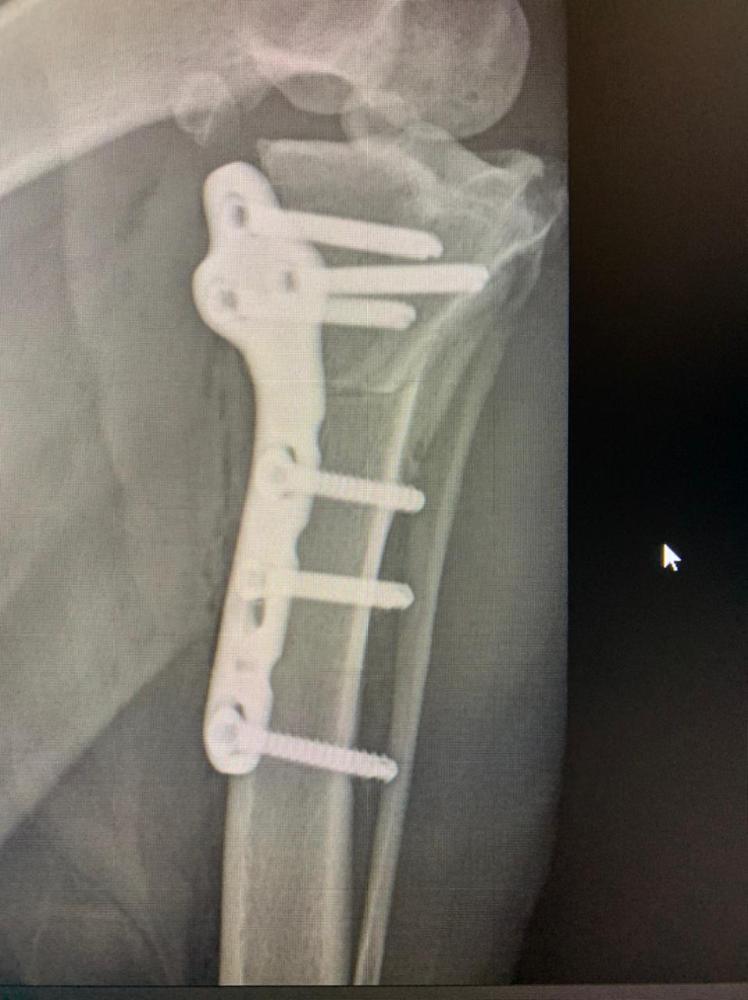

Бэкки Опубликовано 19 февраля, 2021 Опубликовано 19 февраля, 2021 Ну вот мы и дома! Ходит пока на 3 лапках, на лапе, которую оперировали компрессионная повязка, которую не снимать до вс, в воскресенье на приём к хирургу, снимут повязку. Катетер тоже оставили, до завтра, если будет нормально кушать и гулять, завтра снимем. Чувствует себя вроде нормально, покушала и легла спать. Воротник, естественно, жутко не нравится. Пока как-то так. Снимки рентгена: 1 7